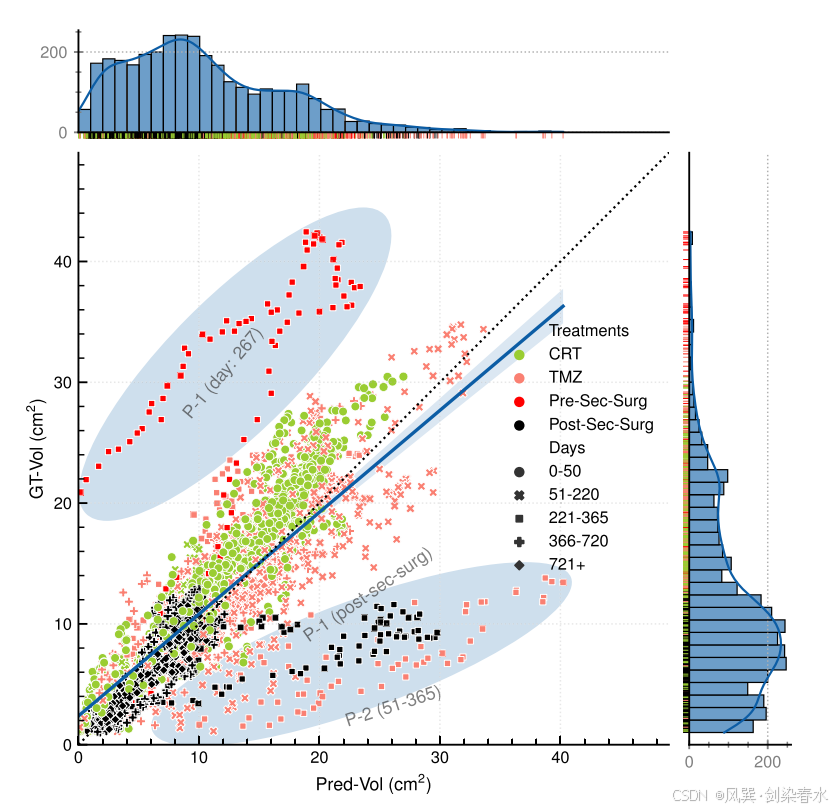

Figure 8 | 基于治疗变量的肿瘤生长预测评价,包括CRT、TMZ、二次手术(分为术前和术后)及其对应的天数范围:治疗类型以不同颜色标记,天数范围用不同标记表示,两个带有注释文本的椭圆突出显示两个异常区域;